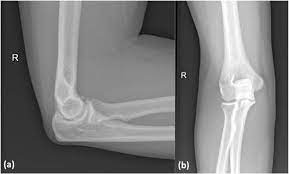

Elbow Arthroscopy

Elbow arthroscopy is a minimally invasive surgery for diagnosing and treating elbow joint problems.It offers advantages like smaller incisions, quicker recovery, and less pain compared to traditional surgery. During the procedure, inserts a thin camera called an arthroscope to see inside the joint on a screen.